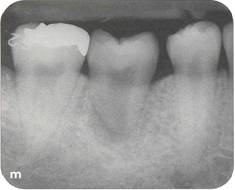

Fi 545e45f g S.3a Panoramic view at the first visit. Maxillary left third molar will be transplanted to the area of nonrestorable mandibular left second molar in a 21-year-old male. |

Fi 545e45f gs S.3b and 5-3c Preoperative view. |

Fi 545e45f gs S-3d and 5-3e Recipient site before extraction. |

Fi 545e45f g 5-3f Three weeks after extraction of the second molar. The recipient site is ready for transplantation. Fi 545e45f g 5-3g The donor tooth. |

Fi 545e45f g 5-3h The extracted donor tooth. The form of the root and the amount of the periodontal ligament are not ideal. Fi 545e45f g 5-3i Suture of the gingival flap and fixation after transplantation. |

Fi 545e45f g 5-3j After transplantation. Fi 545e45f g 5-3k Three months after transplantation. Because healing of the pulp was not achieved, apexification was initiated. |

Fi 545e45f gs 5-3p and 5-3q One year 4 months after transplantation. |

Fi 545e45f g 5-31 Fi 545e45f ve months after transplantation. Fi 545e45f g 5-3m Nine months after transplantation. The calcium hydroxide has been replaced with gutta percha. |

Fi 545e45f g 5-3n The donor tooth before restoration with a ceramic crown. Fi 545e45f g 5-30 The ceramic crown. |